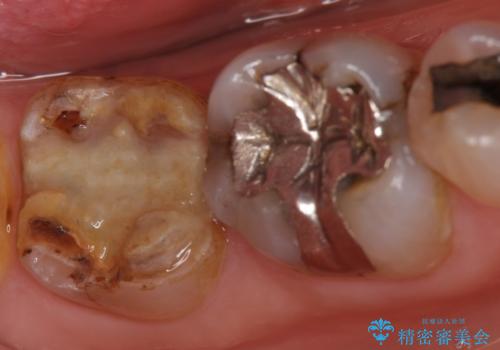

- 右下7の銀歯が外れてしまった方の症例です。

古い樹脂やカリエスを除去後、形を整え、オールセラミッククラウンによる補綴を行いました。